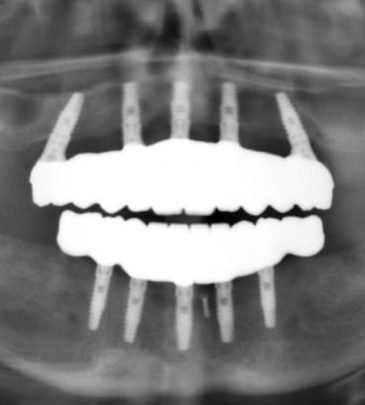

Our team of reputed dental practitioners is committed to ensuring that our courses are relevant, engaging, and reflect the latest advances in dentistry. Our wealth of clinical experience is leveraged through the collaborative effort in teaching fundamental concepts to advanced procedures in restorative dentistry, implantology, orthodontics, and periodontics.